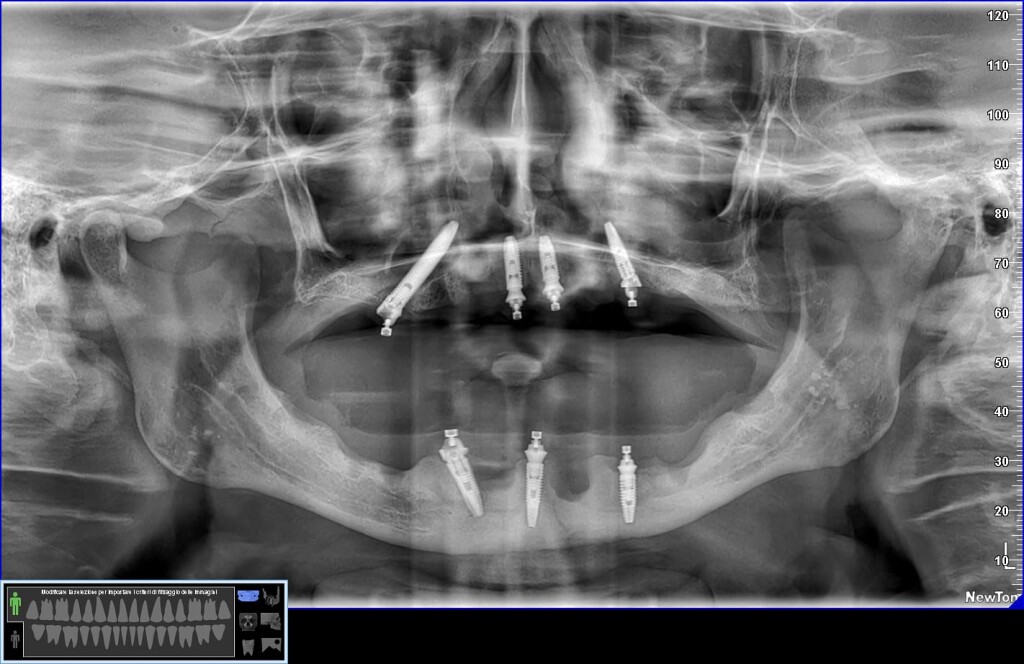

Nel caso di oggi vedremo il posizionamento di un impianto transinusale in questo paziente:

Durante la chirurgia dovrò gestire una perforazione rilevante della membrana del seno.

Ah… questa è la panoramica finale, inferiormente non ho trovato il modo per mettere 4 impianti ma solo tre… vedremo se aggiungerne uno. E non farti ingannare dall’immagine: il mentoniero di destra non è quello che sembra più distale ma quello meno visibile più mesiale.😎